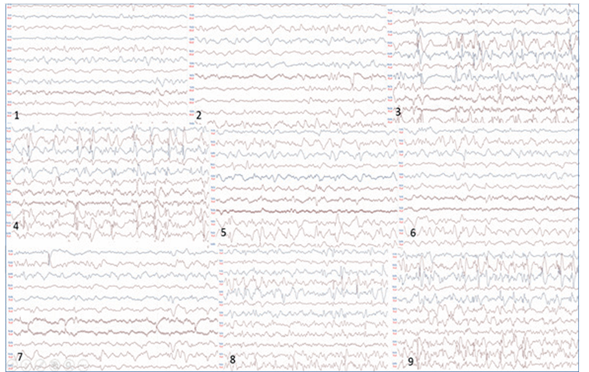

- Polisomnografía con oximetría de pulso: trazado de vigilia y sueño con abundantes espigas y poliespigas, ondas centrales izquierdas con propagación a regiones anteriores que por momentos se organizan en trenes y temporales izquierdas independientes, frecuentes poliespigas ondas fronto-centro-parietales derechas y temporales derechas independientes. Se evidenció una crisis de inicio focal electrográfica. Eficiencia de sueño disminuida. Sin alteraciones respiratorias. Sin movimientos de piernas en rango patológico (Figura 1).

Los pacientes con encefalopatía con alteración del gen KCNQ2 mostraron eficacia a los BCS en el control de las convulsiones. Sugerimos el inicio de tratamiento temprano con BCS en las convulsiones neonatales cuando se sospecha encefalopatía por KCNQ2, en lugar de fenobarbital o levetiracetam, que son los anticonvulsivantes más utilizados en convulsiones neonatales11 (Figura 2).